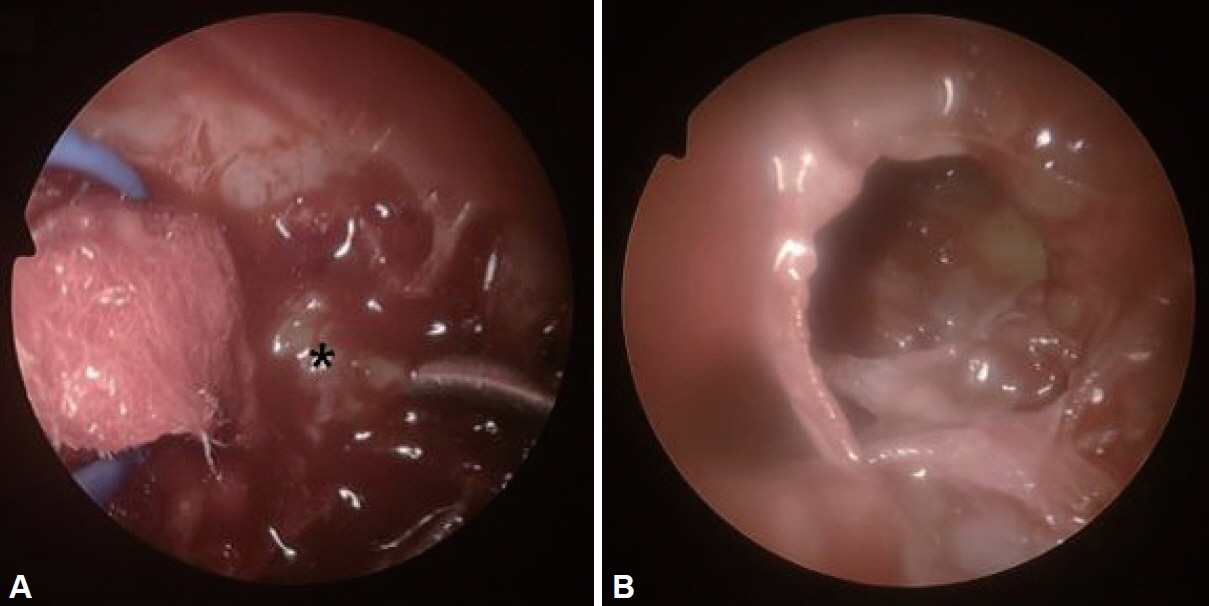

- Schwannomas are benign tumors that can develop in any part of a nerve containing Schwann cells. Skull base schwannomas are rare, representing approximately 4% of extracranial schwannomas. Among these, vidian nerve schwannomas are particularly uncommon, with only a few documented cases. In this report, we describe the case of a 58-year-old female patient who presented with an incidental finding of a skull base mass. The patient’s only symptoms were intermittent headaches and dry eyes. No mass was detected during the physical examination. Radiographic evaluation revealed a neoplasm within the vidian canal, and the lesion’s characteristics suggested a schwannoma. The patient underwent endoscopic resection, and subsequent histopathological analysis confirmed the diagnosis of schwannoma. Follow-up imaging and physical examination showed no evidence of recurrence. This case report highlights a schwannoma located in the vidian canal and extending into the foramen rotundum, which was successfully managed with endoscopic surgery.